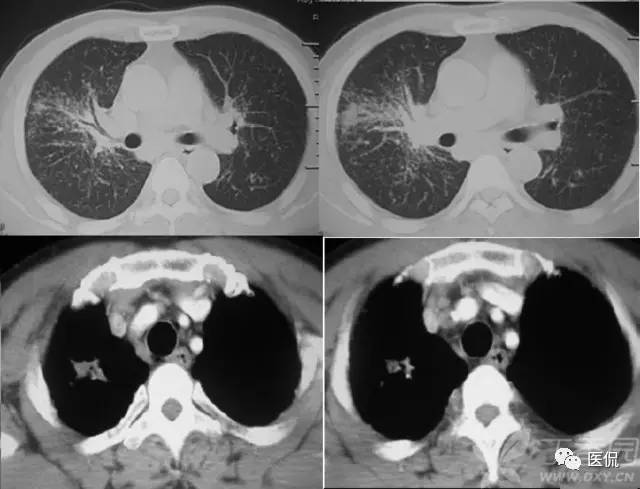

星系征

肺结节病的大结节(直径大于1公分)有无数小结节构成,大结节周围环绕小结节卫星灶,晚期支气管血管周围受累呈条带状,这与天文领域的卫星、慧星、银河很相象,这些影像表现与肺结节病的病理学表现很相似。“星系征”就是用来描述这一影像学表现的一个征象。需要注意的是,具有星系征这一征象的并不仅仅只有肺结节病,有时候,其他疾病如肺结核、肺转移瘤、细支气管肺泡癌及癌性淋巴管炎等也会出现这种征象。

1、小星星状:结节病肺内结节多发于胸膜下、叶间裂旁及沿支气管血管束周围分布,多表现为边缘模糊、不规则的网织结节或小叶中心结节,结节大小2~5 mm ,弥漫在双肺内似聚集在一起的成簇的小星星,此征象应与肺内转移瘤鉴别,转移瘤多发生于双下肺,边缘较光滑,多发孤立结节。

2、卫星状 : Ⅲ期的为肺内弥漫的小结节,大小约1 mm ,融合成大结节后通常可达到1~2 cm 左右,最大为2~4 cm ,边缘不规则,周围可见小的结节卫星灶环绕大结节周围,呈卫星状,中间的大结节酷似太阳,四周酷似它的卫星。

3、慧星状 :肺实质融合的大结节周围可见肺泡性渗出,呈毛玻璃状,好象长长的尾巴。

4、银河状 : Ⅳ期的结节患者,支气管血管周围同时受累,沿支气管血管束周围分布,支气管血管壁呈结节状增厚〔3〕,其间可见含气或扩张的支气管,呈条带状,与正常肺组织之间有清楚的分界上述表现的病理基础是病理变化为主炎性病灶表现:非干酪样肉芽肿和淋巴细胞肺泡炎,主要由上皮细胞组成的肉芽肿结节,体积小,结节内无干酪样坏死,常有多核巨细胞以及散在淋巴细胞,周围较多的淋巴浸润,以后为纤维包绕,结节融合。

肺结核星系征:

肺结节病星系征: